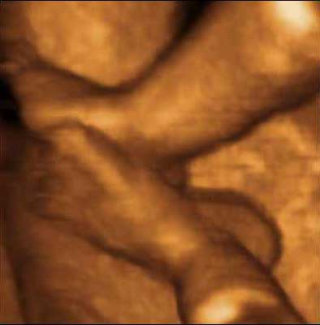

Pies